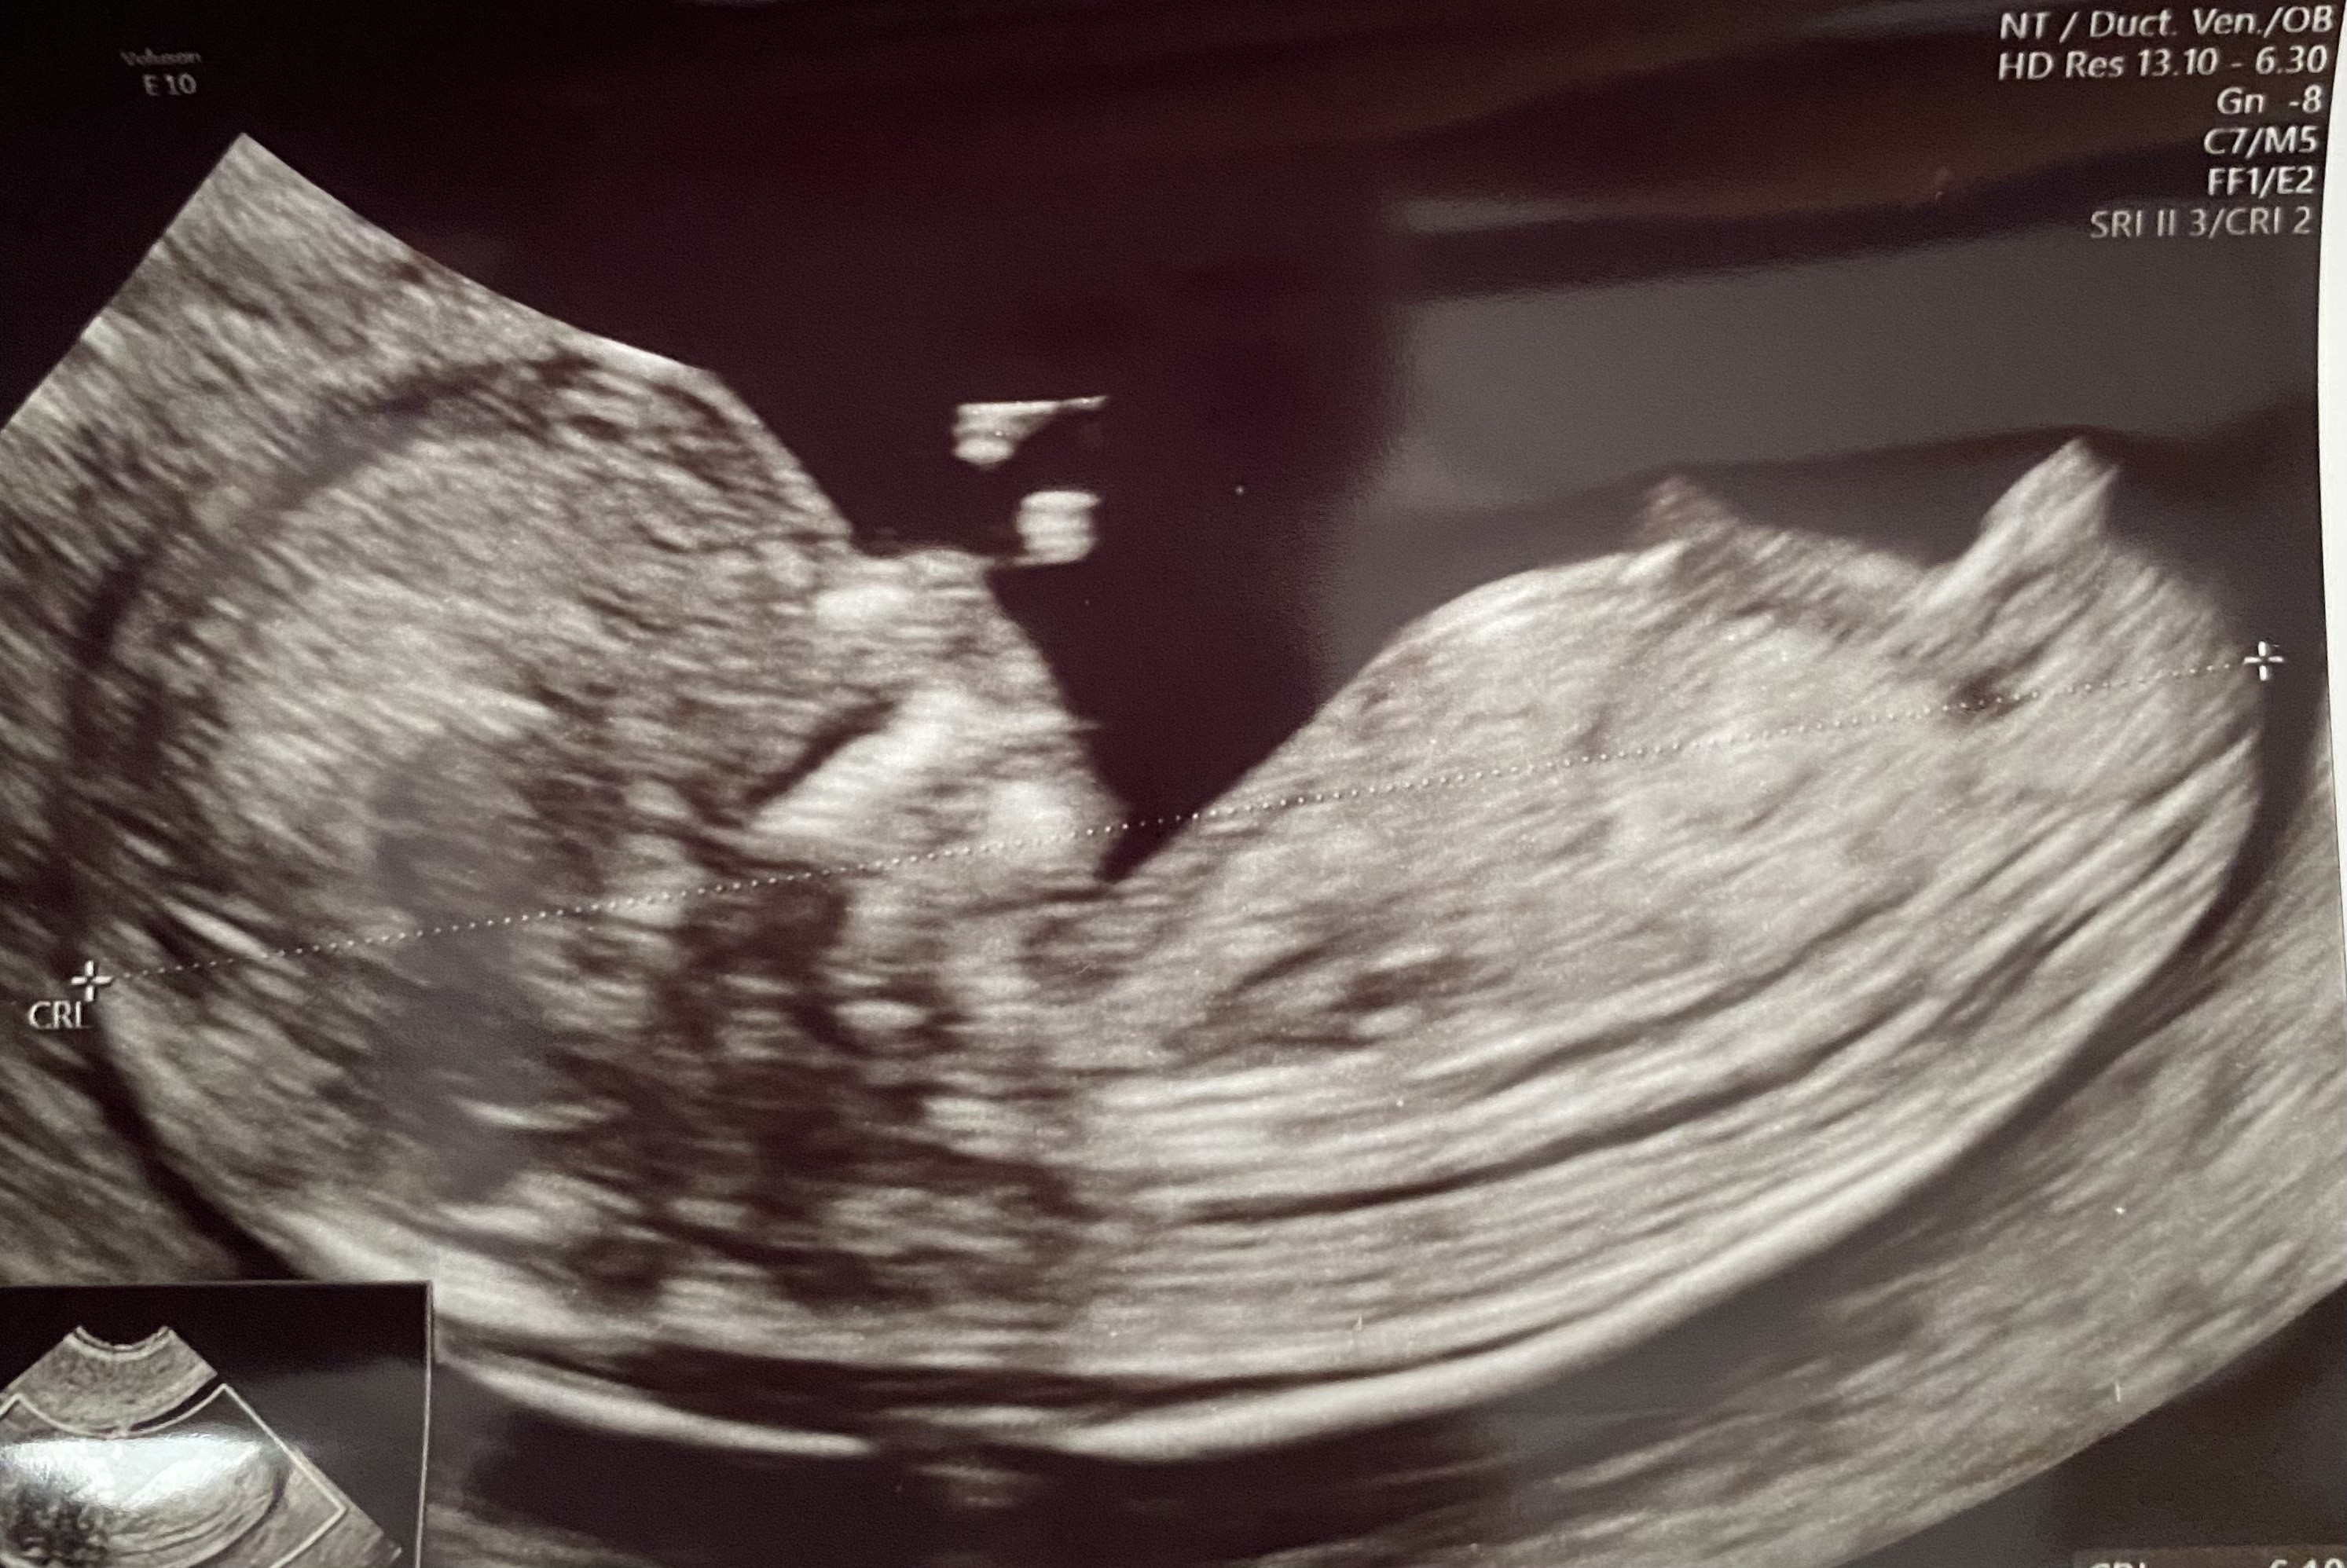

pomimo mojego niskiego białka pappap ryzyko aberracji chromosowych wyszlo niskie 💪. Już dawno nie przeżyłam takiego stresu jak przy prenatalnych 😵‍💫 na szczęście mamy to już za sobą 🙏🏻. Dzidzi zdrowe ma 6,5cm i według lekarza będzie mała laleczka 🥰.

9A4F8C78-81FB-48BF-B01F-E614E6051C5C.jpeg